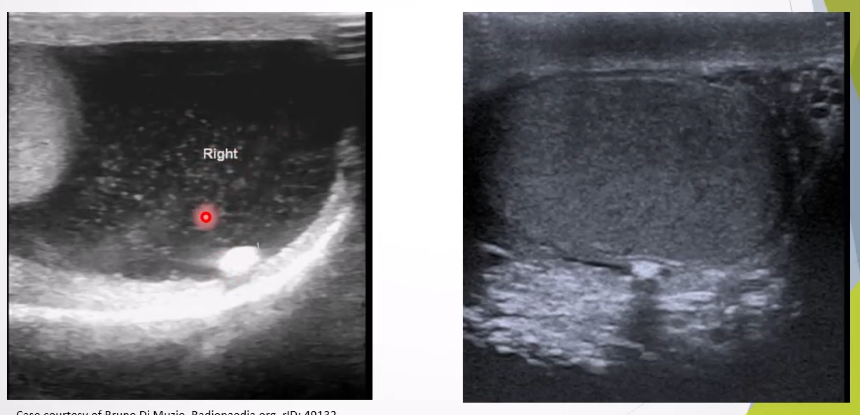

Microlithiasis: Tiny calcium deposits within testes associated with increased risk of testicular cancer.

Clinical Presentation: Usually asymptomatic.

Ultrasound Appearance:

Small non-shadowing hyperechoic foci ranging in diamter from 2-3mm , uniform in size or clustered but can be seen peripherally or segmentally